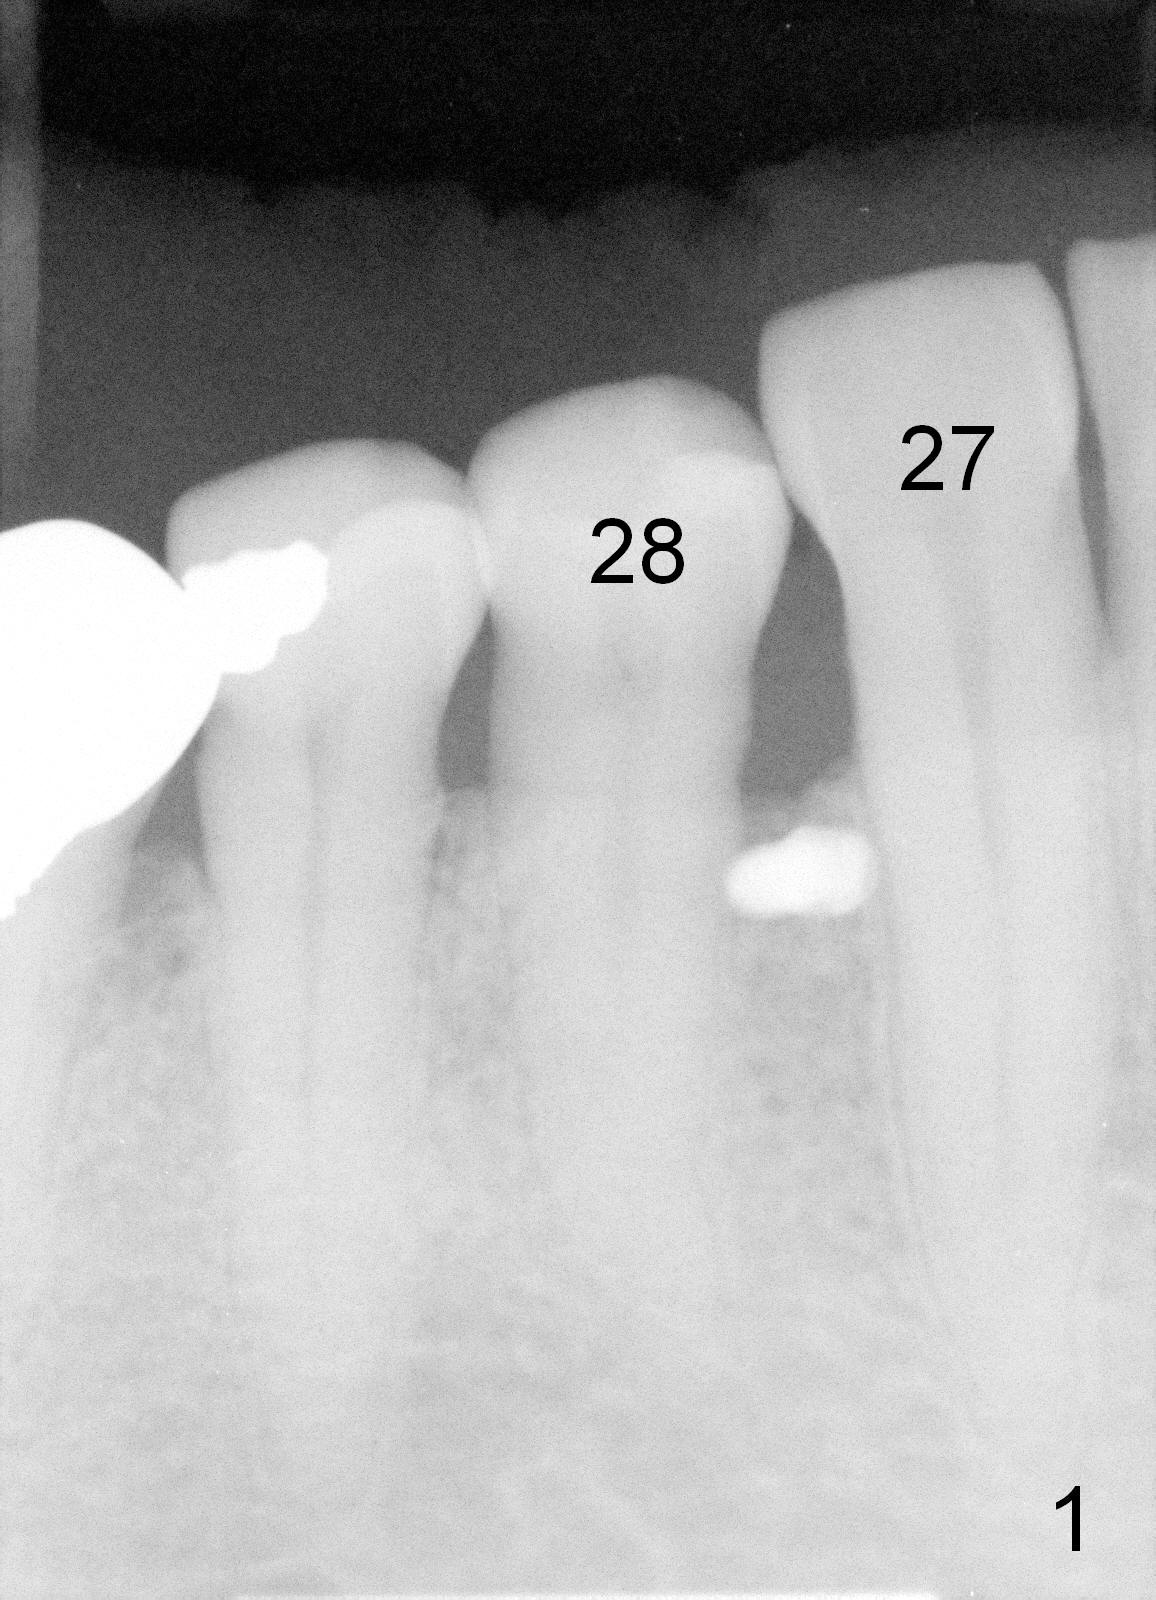

The first two times of mini-implant placement is done without incision or pilot drill. The third time, a vertical incision is made between the teeth #27 and 28 after minimal buccal injection. A pilot drill is placed just coronal to the mucogingival junction (MGJ). It quickly become unstable. An exploration shows that the lingual half of the bone is soft and tender, probably entering the previous osteotomy. Therefore the pilot drill has to be moved slighly apical to MGJ. After penetration of the buccal cortex by the drill, a 1.6x6 mm mini-implant is placed initially (Fig.1). Then the trajectory is changed away from the tooth #28, while the implant is placed deeper. There is great resistance before the implant is fully placed (Fig.2). The patient feels mild discomfort lingually, but there is no sign of lingual plate penetration. Postop, the contact between #28 and 29 is tightened. Cross arch retraction starts immediately.